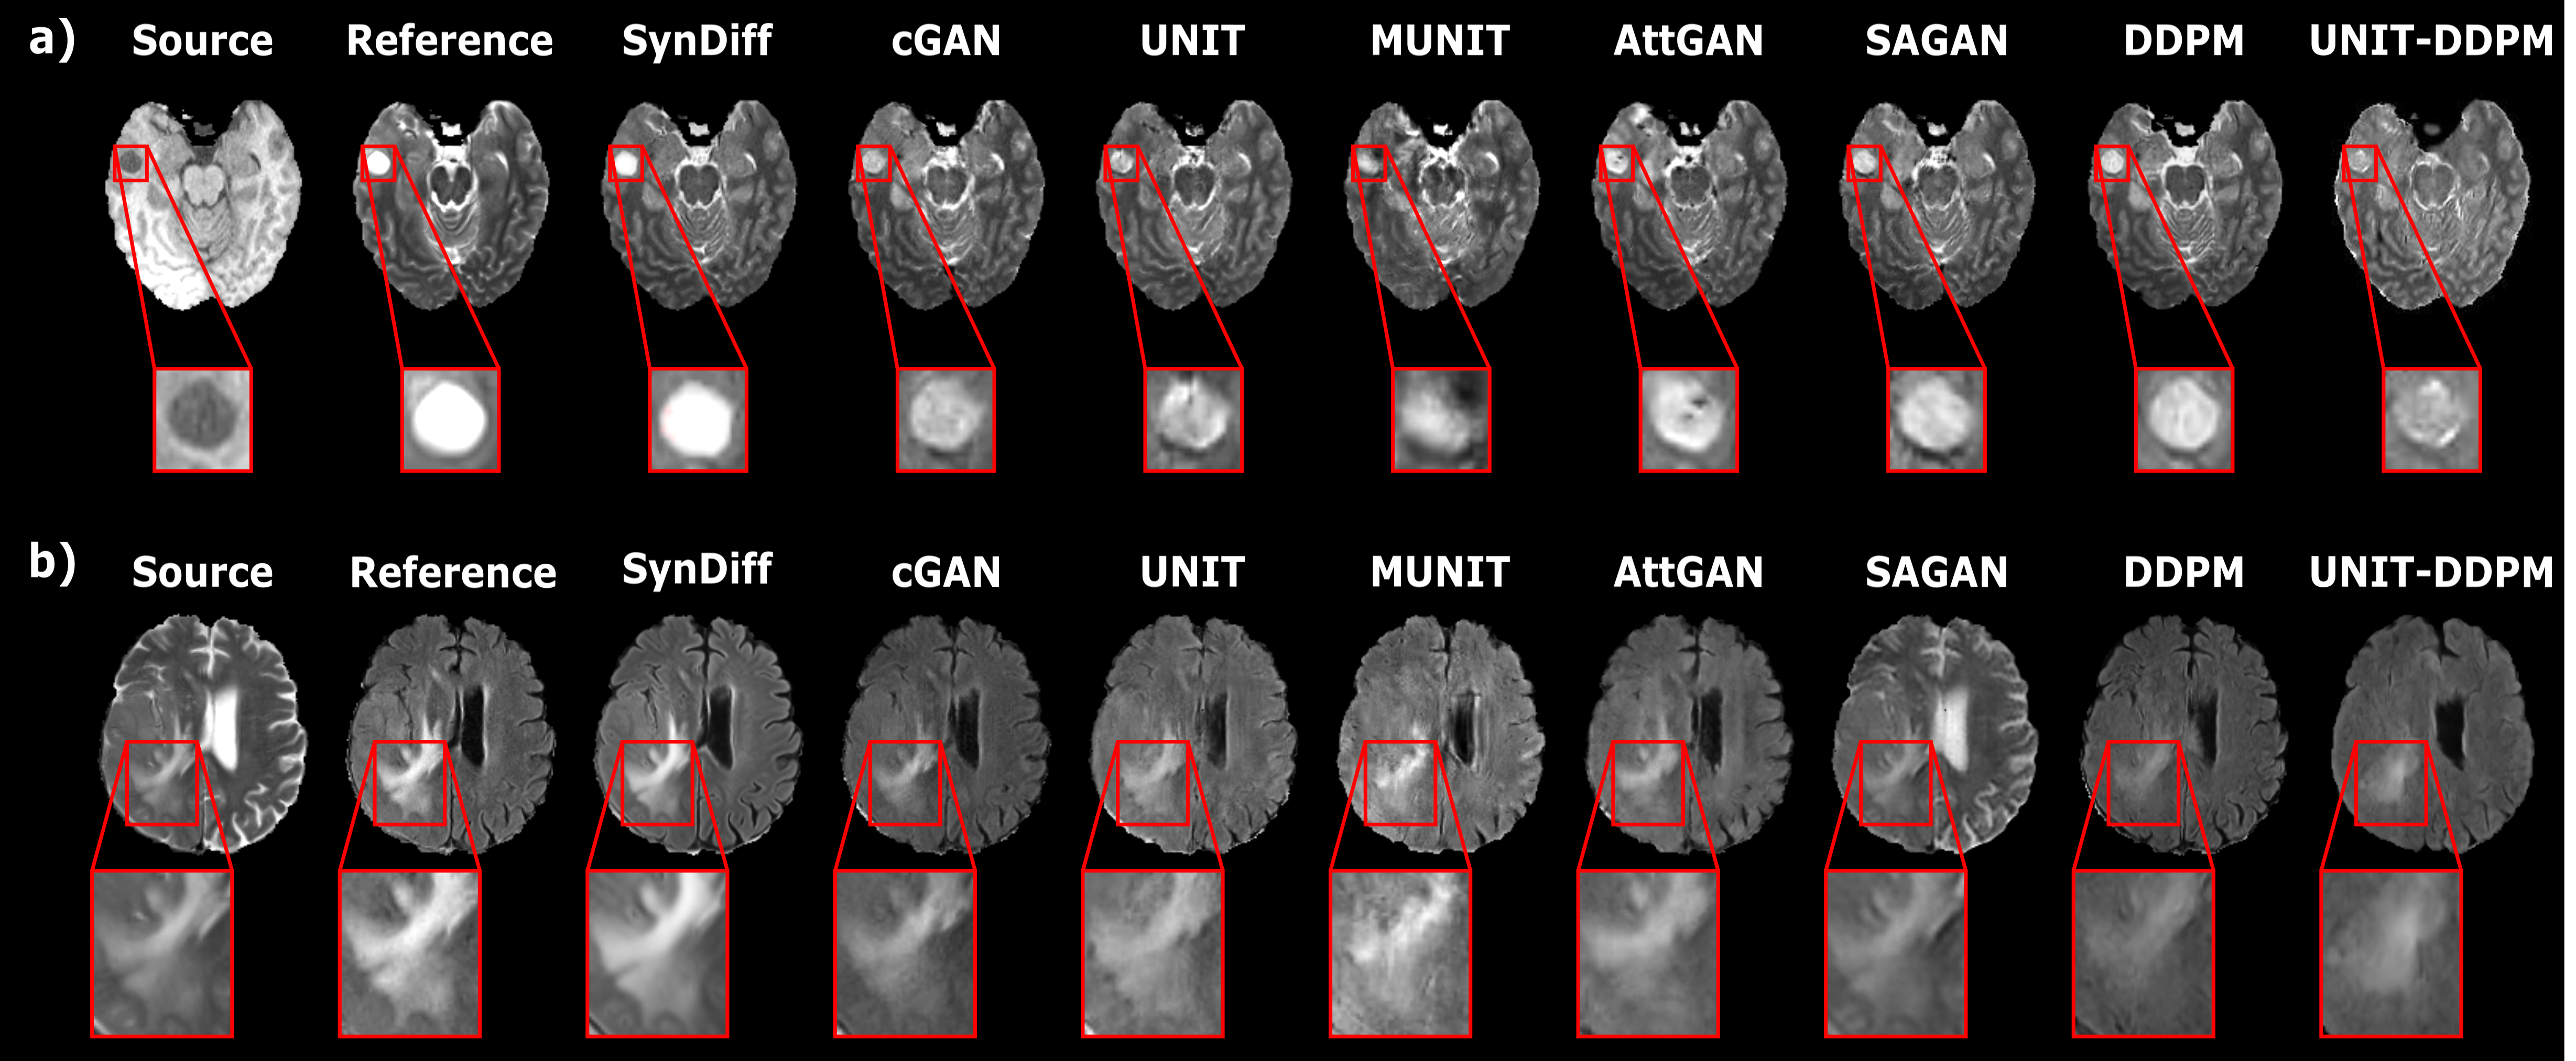

We demonstrated SynDiff for unsupervised MRI contrast translation against state-of-the-art non-attentional GAN (cGAN, UNIT, MUNIT), attentional GAN (AttGAN, SAGAN), and regular diffusion (DDPM, UNIT-DDPM) models. First, experiments were performed on brain images from healthy subjects in IXI. Table 2 lists performance metrics for T2T1, T1T2, PDT1, T1PD, PDT2, and T2PD synthesis tasks. SynDiff yields the highest performance in all tasks (p0.05), except for PDT2 where cGAN performs similarly. On average, SynDiff outperforms non-attentional GANs by 2.2dB PSNR and 2.5 SSIM, attentional GANs by 1.4dB PSNR and 1.2 SSIM, and regular diffusion models by 5.7dB PSNR and 6.6 SSIM (p0.05). Representative images are displayed in Fig. 3. GANs show noise or local inaccuracies in tissue contrast. Regular diffusion models suffer from a degree of spatial warping and blurring. UNIT-DDPM shows relatively lower anatomical accuracy, with occasional losses in tissue features. In comparison, SynDiff yields lower noise and artifacts, and higher accuracy in tissue depiction.

Next, experiments were conducted on brain images from glioma patients in BRATS. Table 3 lists performance metrics for T2T1, T1T2, FLAIRT1, T1FLAIR, FLAIRT2, and T2FLAIR tasks. SynDiff again achieves the highest synthesis performance in all tasks (p0.05), except for cGAN that yields similar PSNR in T1FLAIR, and performs similarly in FLAIRT1. On average, SynDiff outperforms non-attentional GANs by 1.5dB PSNR and 3.5 SSIM, attentional GANs by 2.7dB PSNR and 5.0 SSIM, and diffusion models by 4.2dB PSNR and 6.8 SSIM (p0.05). Representative images are displayed in Fig. 4. Non-attentional GANs show elevated noise and artifact levels. Attentional GANs occasionally suffer from leakage of contrast features from the source image (e.g., hallucination of regions with notably brighter or darker signal levels). Regular diffusion models show a degree of blurring and feature losses. Instead, SynDiff generates high-fidelity target images with low noise and artifacts.